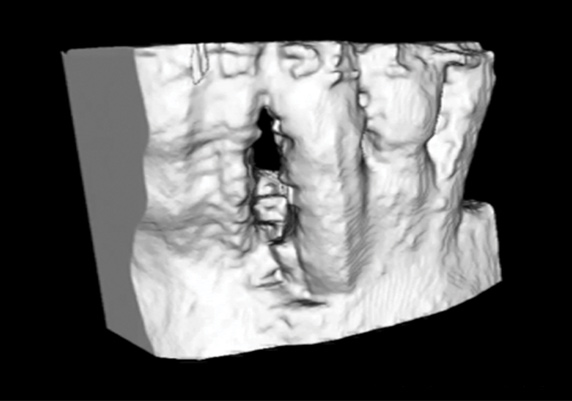

Recently, ixmyelocel-T stem cells were evaluated in a randomized, controlled clinical trial to evaluate sinus floor augmentation with transplantation of autologous cells enriched with stem cells. Ixmyelocel-T is derived from enriched CD90+ and CD14+ bone marrow-derived cell populations and carries a unique expression of markers for tissue repair and regeneration.20 Patients with maxillary sinus bone deficiencies who needed sinus lifting procedures prior to dental implant therapy were allocated to receive either stem cells delivered on a β-tricalcium phosphate scaffold or the scaffold alone. Four months after the surgery, findings from histology and cone-beam computed tomography (CBCT) analyses indicated that stem cell therapy yielded better regenerated bone quality than standard-of-care matrix alone (Figure 1 and Figure 2).20 By targeting specific signaling pathways, oral tissue regenerative outcomes may be improved through delivery of stem cells to increase bone regeneration.

Fig 2. Representative images of 3D reconstructions of the maxillary sinus cavity of the skull show the bone volume that was grafted (blue areas) in the control (Fig 1) and stem cell therapy (Fig 2) groups in bony defects. Histological and corresponding micro CT images of bone biopsies harvested from the grafted regions of the two groups show a greater degree of mineralized bone tissue in the stem cell therapy group (Fig 2). (Images reprinted with permission from Kaigler D, Avila-Ortiz G, Travan S, et al. J Bone Miner Res. 2015;30[7]:1206-1216.)

Figure 2